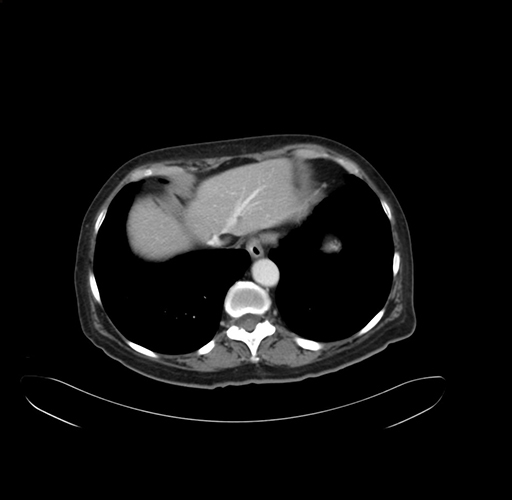

Pre-Chemo: Axial Venous

Axial Venous